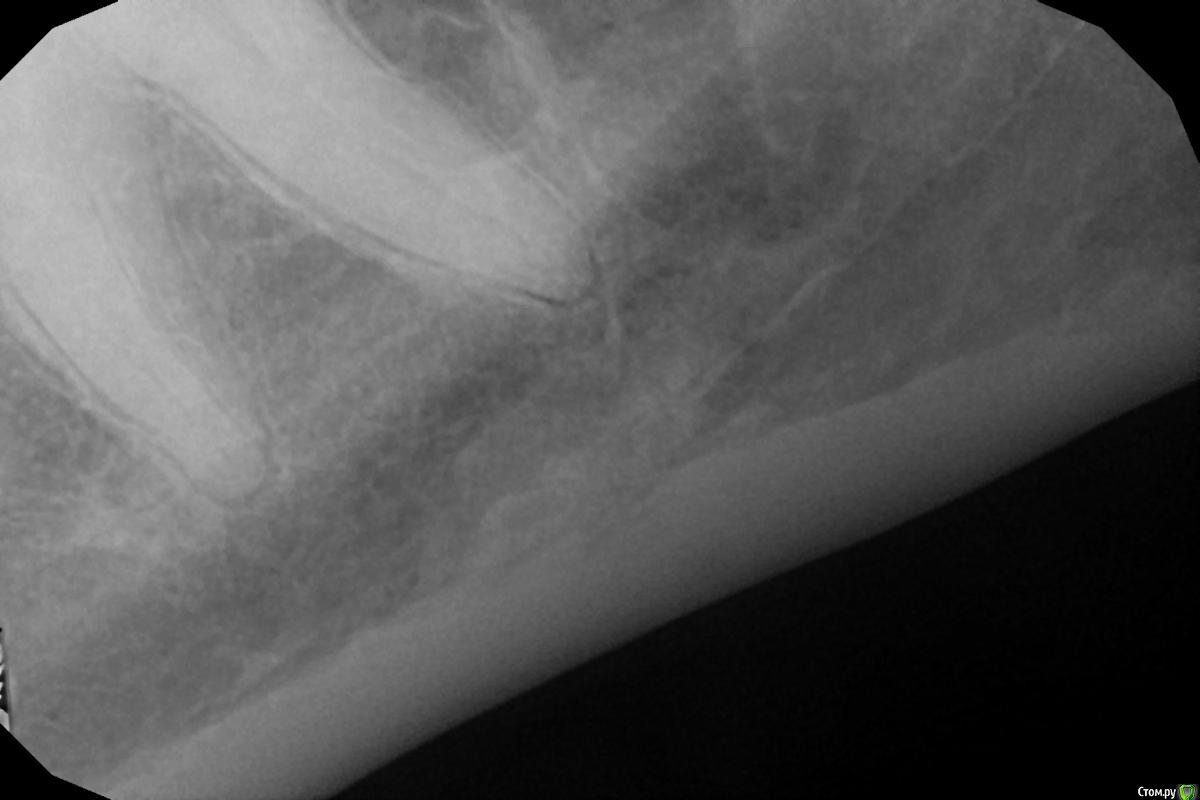

Фарид Расулыч Опубликовано 22 декабря, 2014 Поделиться Опубликовано 22 декабря, 2014 Свежий урожай) только с "грядки" 10 Ссылка на комментарий